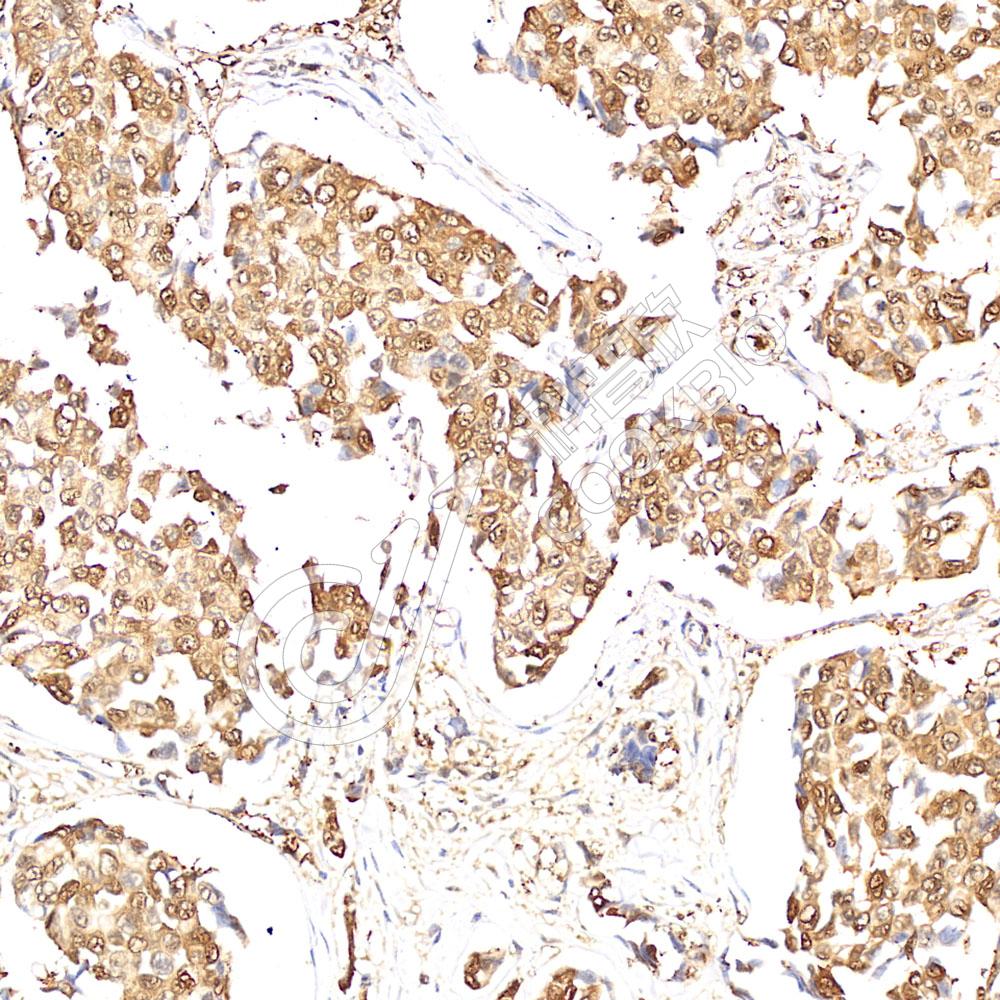

IHC检测Hsp70蛋白(货号 K545732).

样品: 人乳腺癌, 4%多聚甲醛 (货号KSG1101) 固定12-24小时.

抗原修复: 柠檬酸抗原修复液(干粉, pH 6.0) (KSG1201), 高压锅均匀喷气计时2分钟.

—抗: 1: 800稀释, 4℃ 孵育过夜.

二抗: S-vision免疫组化多聚二抗(山羊抗兔),即用型 (货号KB3906), 室温孵育20分钟.